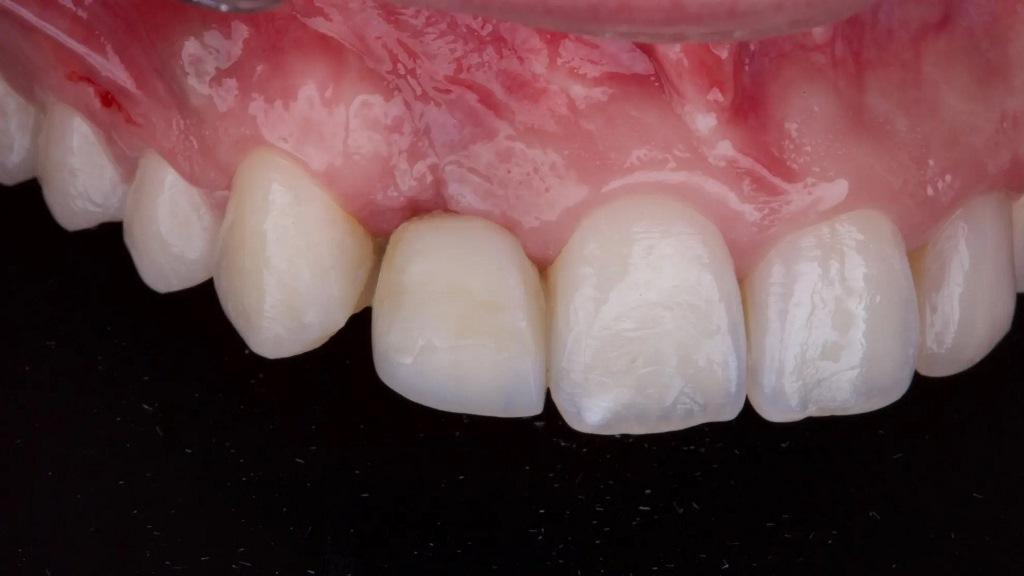

Примерно через три месяца был сделан окончательный слепок, и была изготовлена окончательная циркониевая коронка с керамическим покрытием, которая была закреплена на титановом гибридном абатменте (фото 9). Окклюзия была тщательно скорректирована, и пациентка была включена в структурированную программу технического обслуживания с четырехмесячными интервалами восстановления. В течение года наблюдения имплантат продемонстрировал отличные клинические и рентгенологические результаты, продемонстрировав стабильность мягких тканей и отсутствие признаков воспаления или потери костной массы. Пациентка сообщила о полном удовлетворении эстетическими и функциональными результатами.

Фото 9: Окончательное протезирование: коронка из диоксида циркония с фарфоровым покрытием закреплена на титановом соединительном абатменте.